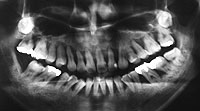

正常な骨の状態(根のまわりを白いモヤモヤ(骨)がおおっています)

骨が溶けてなくなっています(20代女性)(根のまわりが黒く、骨がありません)

なぜなら、レントゲンを撮れば骨が溶けているか、溶けていないかがわかります。

どこの骨が溶けているのか、溶けていないのか場所がわかります。

それがわかるのでどこの歯が重症か、悪化しているのかがわかるわけです。

どこの部分の歯周病菌の種類を調べてやればいいのか、わかるのです。

そこの歯周病菌の種類を調べてやれば大体、口の中は感染症だから原因の歯周病が何かわかるわけです。